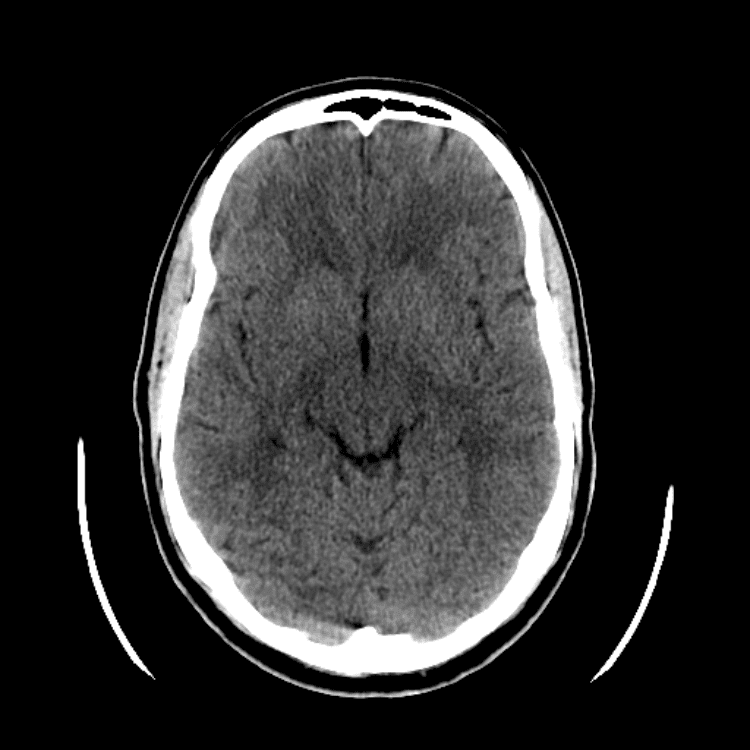

Practice

Simulates call by including subtle or difficult cases and some normals.